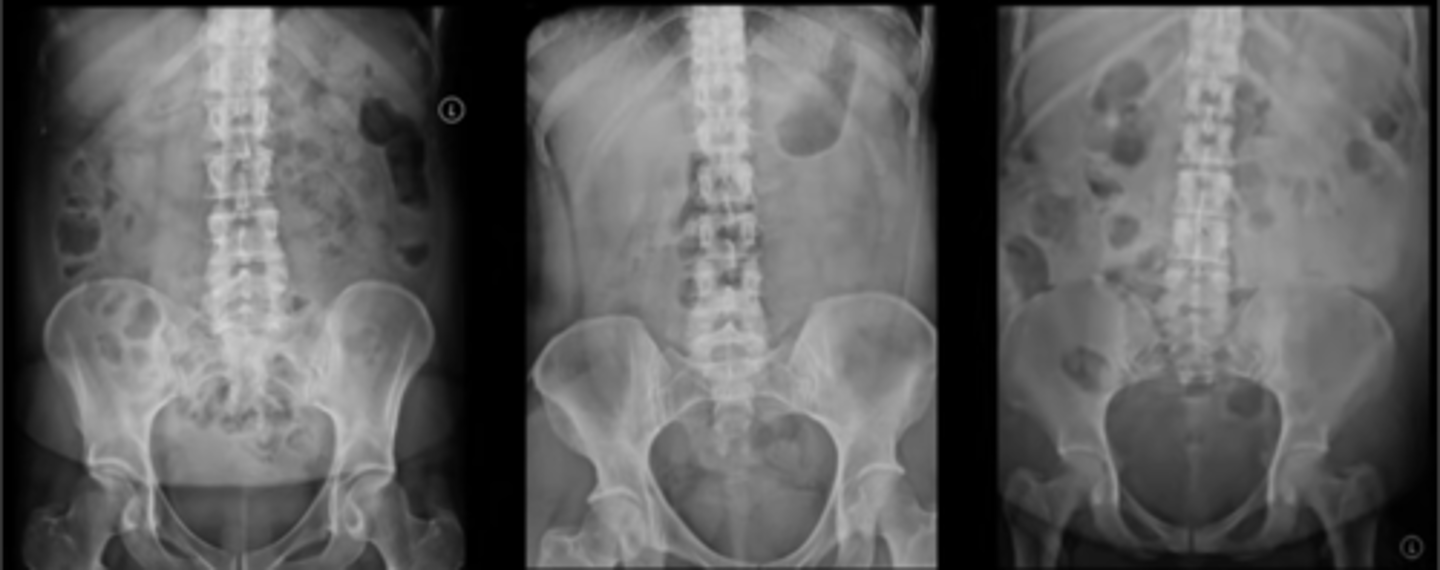

Normal prone AXR

Normal AXR (and normal size liver)

Normal AXR (and normal organs)

Normal AXR (and normal structures)